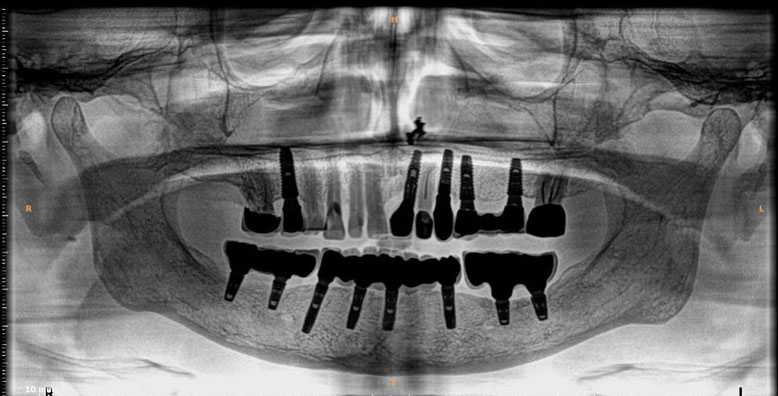

Dental implants are artificial tooth roots use to replace decayed or missing teeth. They are a popular and effective long-term solution, dental implants are placed into the jawbone, providing a stability for replacement teeth.

They serve great benefits like enhancing one's smile and facial structure, provide stability and support allowing to eat and speak freely.

They can last upto several years to a lifetime preventing bone loss and maintains the health of adjacent teeth too.